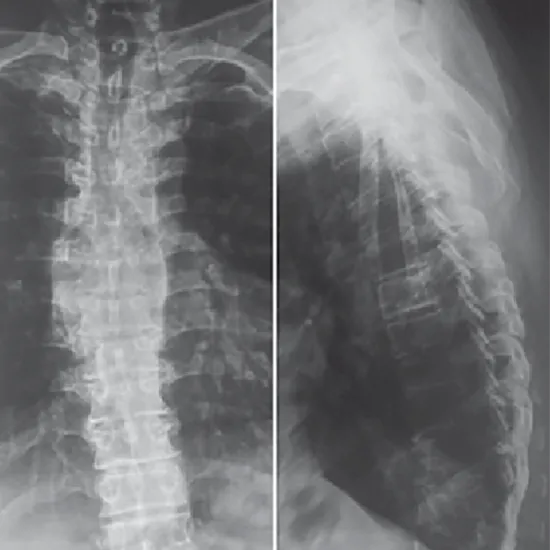

An X-Ray Dorsal Spine LAT View is a non-invasive assessment that allows you to see the twelve thoracic vertebrae (T1 - T12) that comprise the middle portion of your spine.

The X-ray Dorsal Spine LAT View identifies the cause of severe back pain and searches for lesions or fractures to the spinal bones (vertebrae). Identify any malignancies, arthritis, osteoporosis, or suspected spinal infections. Additionally, evaluate the spine for curvature abnormalities, such as lordosis, kyphosis, scoliosis, and birth defects.